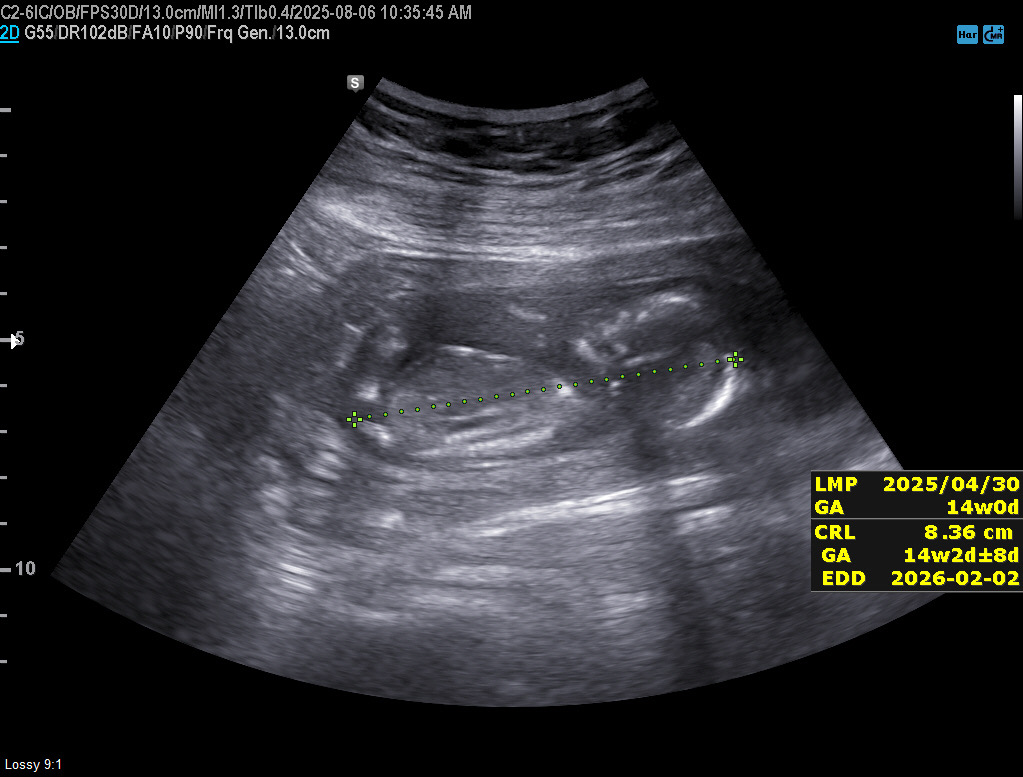

14주 성별 구분 될까요?

오늘 14주 인데 혹시 각도법으로 성별 구분 될까요? 넘 궁굼하네요